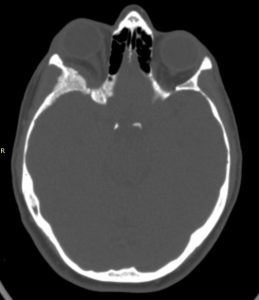

Ασθενής γυναίκα, 41 ετών με εξόφθαλμο δεξιά.

H Μαγνητική & Αξονική Τομογραφία εγκεφάλου ανέδειξε χωροκατακτητική εξεργασία στην περιοχή της πτέρυγας του σφηνοειδούς οστού, δηλ. του άνω (οροφή) και του πλαγίου τοιχώματος του οφθαλμικού κόγχου. Η εξεργασία επεκτείνονταν κατά μήκος της σκληράς μήνιγγας ενώ στην περιοχή του κροταφικού πόλου παρουσίασε ενδοκρανιακή επέκταση. Η πάχυνση του οστού του κόγχου προκαλούσε πίεση των περιεχομένων του κόγχου με αποτέλεσμα εξόφθαλμο.